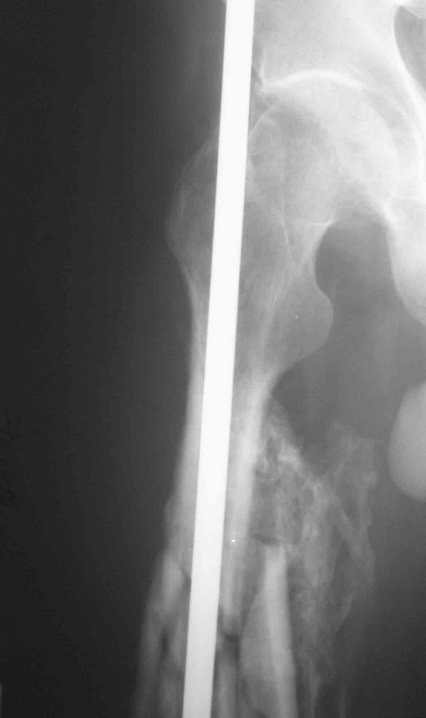

Re: 32- летний пациент с переломами обоих бедер по

Иллюстрации к сообщению